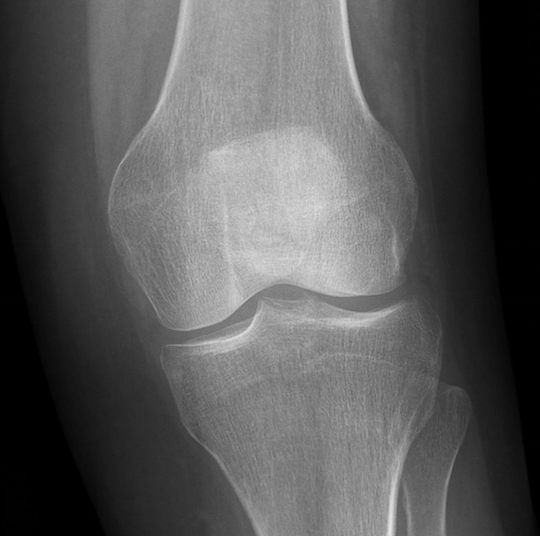

Eco musculoesquelético: Se visualiza línea hiperecogénica que atraviesa perpendicular a la cortical compatible con fractura de rótula. Tendón rotuliano ligeramente anecoico en inserción, sin datos de rotura.

Se solicita Rx para completar estudio.

Fractura de polo inferior de rótula.

Ante los hallazgos se deriva a Urgencias de Traumatología donde confirman diagnóstico.